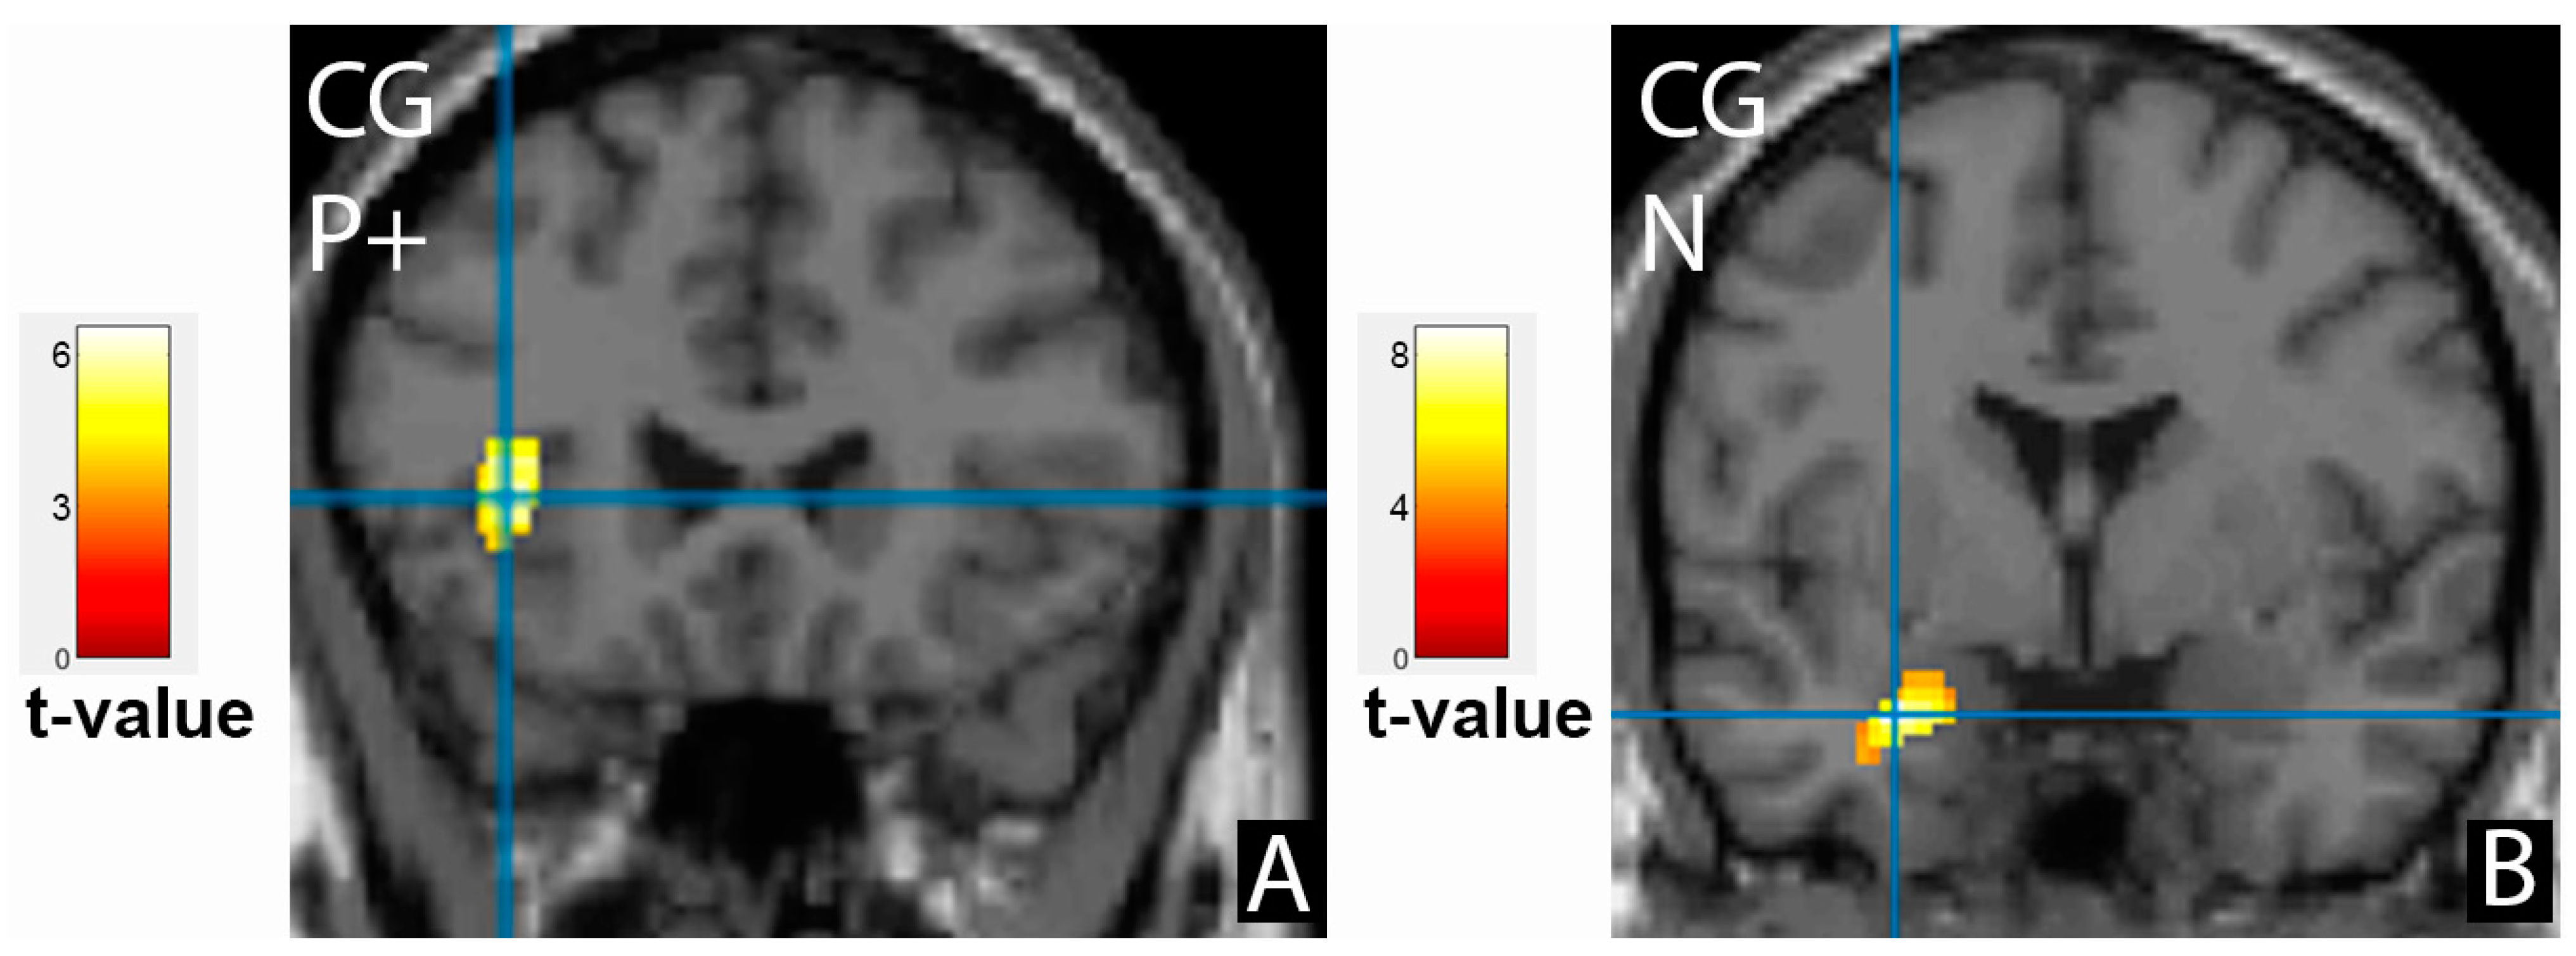

3.3. Comparison of Brain Activation Patterns in Patients before Treatment and Healthy Controls

| Cluster Location | Emotion | Extent | t-Value | p (FWE Corrected) | MNI Coordinates |

|---|---|---|---|---|---|

| Control group, cortical activation | |||||

| Frontal cortex | |||||

| Right middle frontal gyrus | N | 2228 | 8.91 | <0.001 | 54;14;34 |

| Right inferior frontal gyrus, precentral gyrus | N- | 946 | 6.05 | <0.001 | 42;6;30 |

| Right inferior frontal gyrus | P+ | 280 | 7.29 | 0.041 | 46;36;8 |

| Left inferior frontal gyrus, insula | P+ | 358 | 5.93 | 0.014 | −36;24;4 |

| Limbic lobe | |||||

| Left amygdala | N | 298 | 8.29 | 0.009 | −28;0;−24 |

| Occipital cortex | |||||

| Left middle occipital gyrus | N | 2977 | 9.13 | <0.001 | −40;−78;0 |

| Right fusiform gyrus, BA37 | P+ | 3809 | 12.41 | <0.001 | 36;−72;−20 |

| Temporal cortex | |||||

| Left superior temporal gyrus, BA22 | N- | 1689 | 8.4 | <0.001 | −50;14;−6 |

| Control group, cortical deactivation | |||||

| Right limbic lobe, cingulate gyrus, precuneus | N | 2851 | 9.49 | <0.001 | 6;−56;28 |

| Left limbic lobe, cingulate gyrus, BA31, precuneus | N- | 159 | 4.93 | 0.043 | −10;−58;24 |

| Left limbic lobe, cingulate gyrus, BA23 | P+ | 143 | 4.61 | 0.072 | −2;−36;30 |